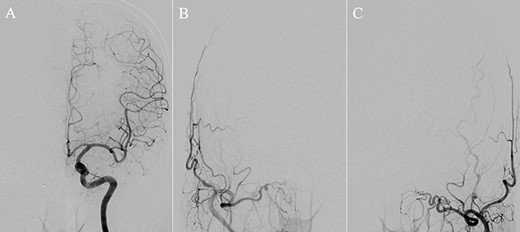

A patient in their 70s with extracranial lymphoma was incidentally found to have ACF–dAVF via head computed tomography and magnetic resonance angiography. Digital subtraction angiography (DSA) confirmed ACF–dAVF with multiple feeding branches, arising from bilateral OphAs, distal IMAs and the left middle meningeal artery (MMA), with cortical venous reflex (Borden type III, Cognard type IV) (Fig. 1). At the patient’s request, we chose endovascular, rather than surgical, treatment. We injected a 20% N-butyl-2-cyanoacrylate (NBCA)–lipiodol mixture into the fistula through bilateral ethmoidal arteries and the left MMA after we placed coils at the terminal branch of the right OphA. However, we could not achieve full penetration into the fistulous connections because of pressure secondary to high flow from the IMA branches, which resulted in incomplete obliteration (Fig. 1). Four months later, we repeated TAE by temporarily reducing nasal blood flow by inserting gauze infiltrated with xylocaine and epinephrine into the nasal cavities. After introducing the guiding catheter, an endonasal surgeon inserted X-ray-detectable surgical gauze infiltrated with 1% xylocaine and epinephrine (1:10 000) into bilateral nasal cavities using a nasal speculum, while paying full attention to avoid damage to the nasal mucosa. Then, we confirmed that the gauzes were placed in appropriate locations in the upper nasal cavity under fluoroscopic guidance. Immediately after insertion, we were able to confirm decreased blood flow from the IMA using DSA (Fig. 2). After this procedure, we navigated a DeFrictor Nano Catheter (Medico’s Hirata, Osaka, Japan) into the terminal branch of the OphA, which was connected to the dorsal nasal artery. Even though there was still a distance from the tip of the microcatheter to the shunt pouch, the NBCA reached the shunt point and penetrated the venous portion (Fig. 3). Follow-up DSA demonstrated complete obliteration of the ACF–dAVF, and blood flow in the nasal mucosa from the IMA branches recovered normally (Fig. 4).

Angiographic images, anteroposterior (A) and lateral (B) views, showing the microcatheter (arrow) navigated into the terminal branch of the left terminal branch of the ophthalmic artery, which connects to the dorsal nasal artery. Digital subtraction angiography, anteroposterior (C) and lateral (D) views, showing NBCA injected via the microcatheter (arrow) penetrating into the shunt point (arrowhead) without reflux of the NBCA. (E) Three-dimensional reconstruction of the skull showing the NBCA cast (arrow), which was embolized via the dorsal nasal artery.